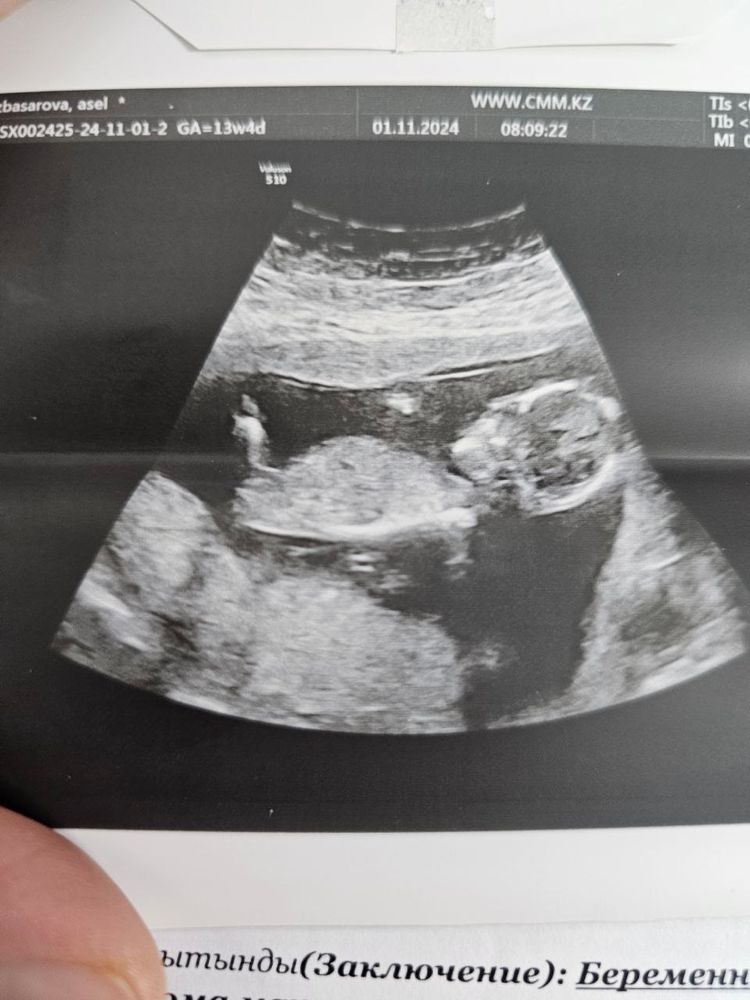

Определение пола 13 недель. На узи сказала пока не понятно. Кто будет?)